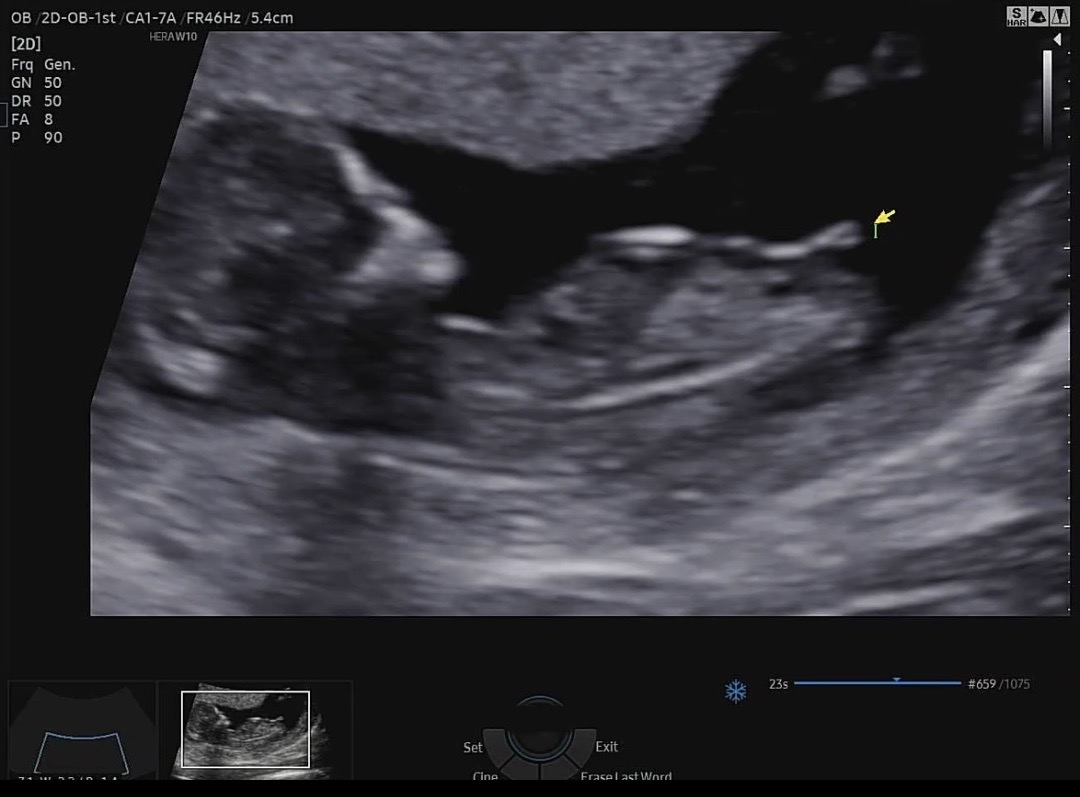

12주 0일 각도법 같이 봐주세요

오늘 기형아 검사하고 특수초음파 했는데 성별이 너무너무 궁금하네요 각도법 잘보시는분들 계신가요??